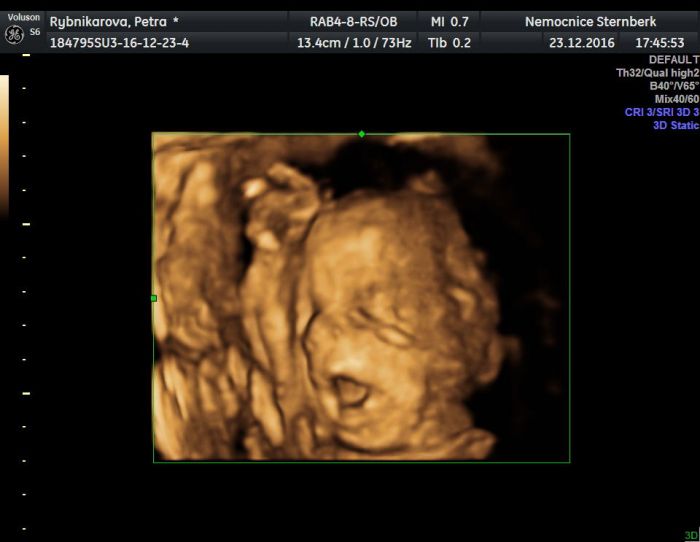

Ahoj holky Smile Taky všem přeji krásné Vánoce, hlavně hodně zdravíčka a pohody SmileVčera jsme byli na 3D a Adámek měl zrovna nejvíc napilno. Pořád se vrtěl, takže většina fotek je rozmazaná. Ale 3 pěkné jsme vybrali, jednu přikládám. Zrovna otvíral pusinku a pořád měl ruku u hlavičky, snažil se krýt Laughing Mějte se krásně :))